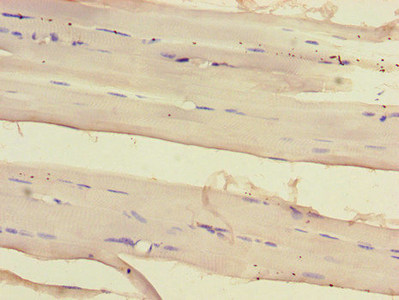

IHC image of CSB-RA061500A0HU diluted at 1:100 and staining in paraffin-embedded human skeletal muscle tissue performed on a Leica BondTM system. After dewaxing and hydration, antigen retrieval was mediated by high pressure in a citrate buffer (pH 6.0). Section was blocked with 10% normal goat serum 30min at RT. Then primary antibody (1% BSA) was incubated at 4°C overnight. The primary is detected by a Goat anti-rabbit polymer IgG labeled by HRP and visualized using 0.05% DAB.

Immunohistochemistry of paraffin-embedded human skeletal muscle tissue using CSB-PA812889LA01HU at dilution of 1:100